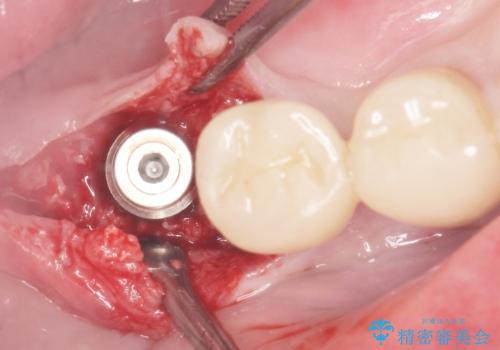

- 奥歯の違和感を主訴に来院された患者様です。

精査したところ、右下の奥歯は大きなう蝕により保存不可能な状態でした。

患者様のご希望により、抜歯後インプラント治療を行いました。